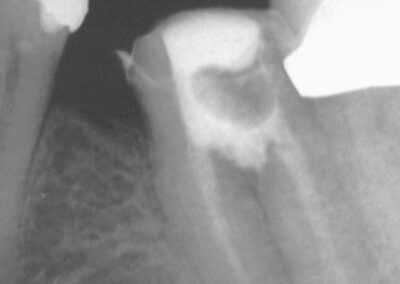

July 2001- Zustand nach prov. WF mit Calxyl. Der Entzündungsprozess ist deutlich rückläufig. Die Fistel ist klinisch geschlossen. Man sieht deutlich, dass der Zahn in der Mitte perforiert ist (Klick!).